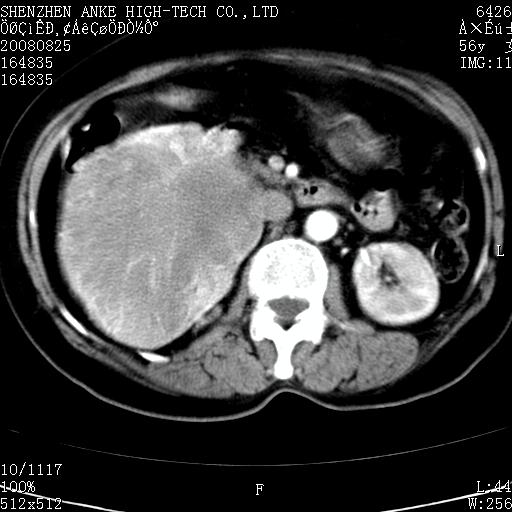

患者,女性,56岁,腰痛3年,查:右腹部约8x10cm肿块,固定,无压痛;8月23日在外院做了平扫,发现右肾巨大肿块(外院具体诊断不祥);今天在我院做了静脉肾盂造影,示:右肾明显增大,分泌功能明显减弱。

1)考虑右肾癌并右肾静脉瘤栓形成。2)脂肪肝。